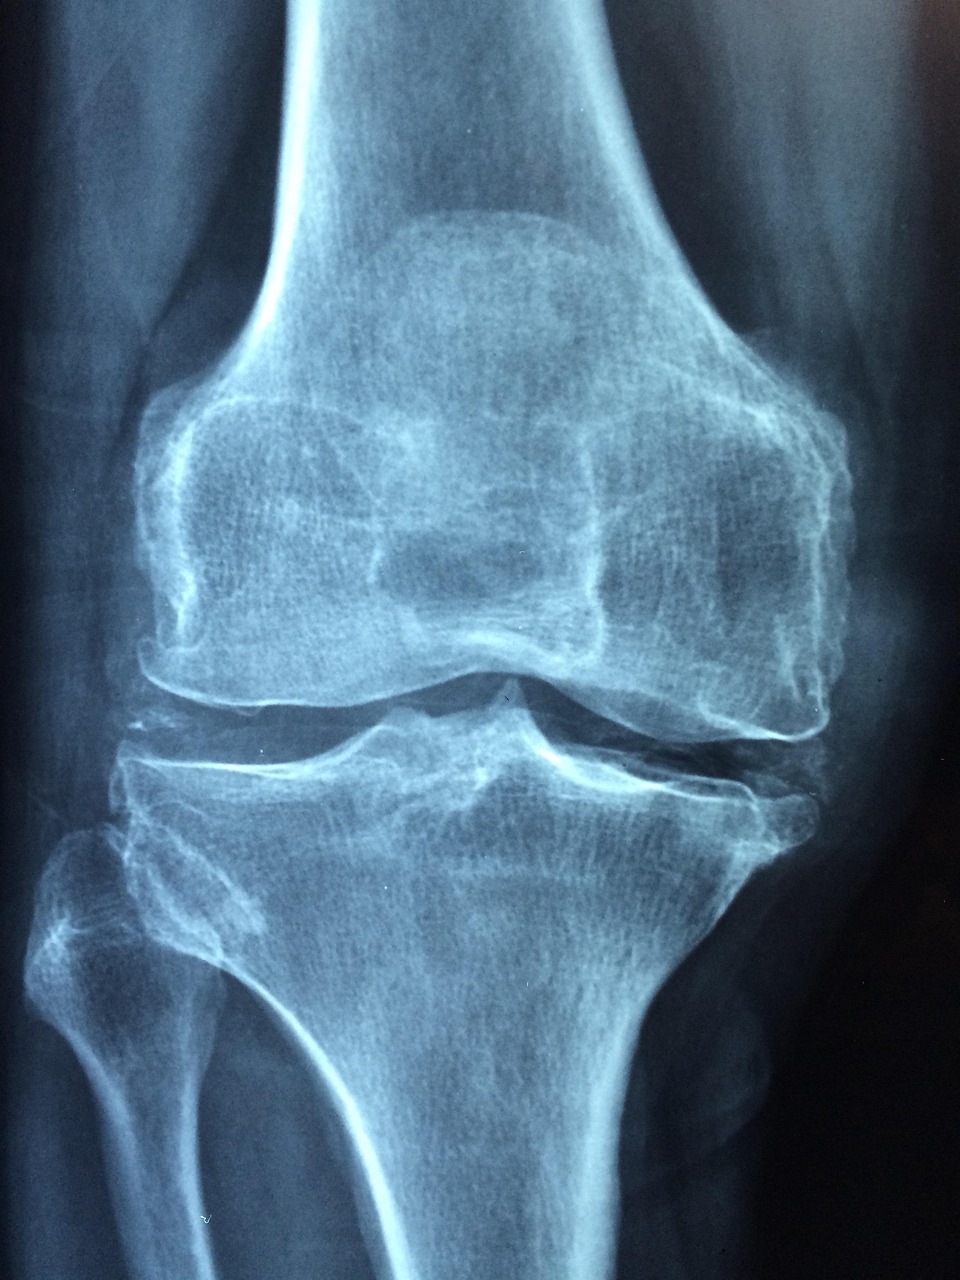

Arthrose : comment soulager les douleurs articulaires ?